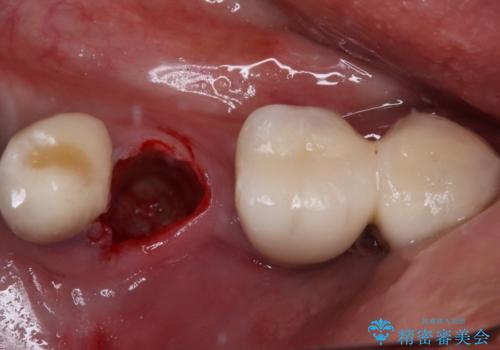

- 奥歯が割れてしまい、抜歯が必要となった患者様です。

以前にも歯が割れてインプラント治療を行いましたが、抜歯してからインプラント埋入→仮歯装着までに半年以上を要し、その間に残された歯への負担が大きくなり、左右反対側のセラミッククラウンが破折したことがありました。

そのため、当院に新しく導入した手法により、抜歯をした日にインプラントを埋入し、そのままを仮歯を装着することで、他の歯への負担を軽減する計画を立てました。